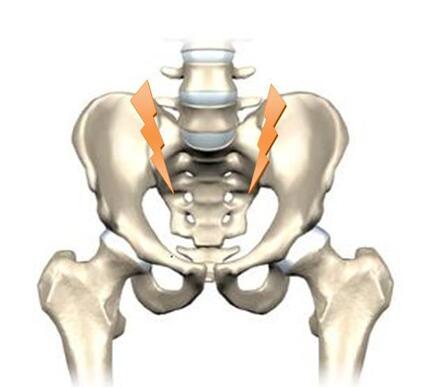

Smerter og stivhed i ryggen

Symptomerne begynder hos de fleste med snigende smerter og stivhed lavt i lænden. Smerterne kan være svære at lokalisere og kan veksle i intensitet fra dag til dag og også i løbet af dagen. Oftest starter smerterne før 40-årsalderen, hos nogle allerede i barnealderen. Smerterne er hyppigst lokaliseret lavt i lænden, dybt inde i balderne og kan stråle ned bag på lårene. Smerterne kan veksle fra side til side og er ofte udløst af sygdomsaktivitet i de bagerste bækkenled (sacro-iliaca-leddene). Symptomerne kan dog komme fra alle dele af rygsøjlen fra nakke og ned til haleben.

Ofte beskriver patienterne det sådan, at smerten vækker patienten i de tidlige morgentimer, og at det bliver bedre, hvis man kommer op at stå op eller gå omkring. Der vil desuden være tydelig morgenstivhed i ryggen, ofte mere end 1 time. Det er typisk, at fysisk aktivitet hjælper på smerterne, og at hvile ikke har nogen virkning. Mange har oplevet, at ibuprofen og lignende gigtmedicin lindrer smerterne.